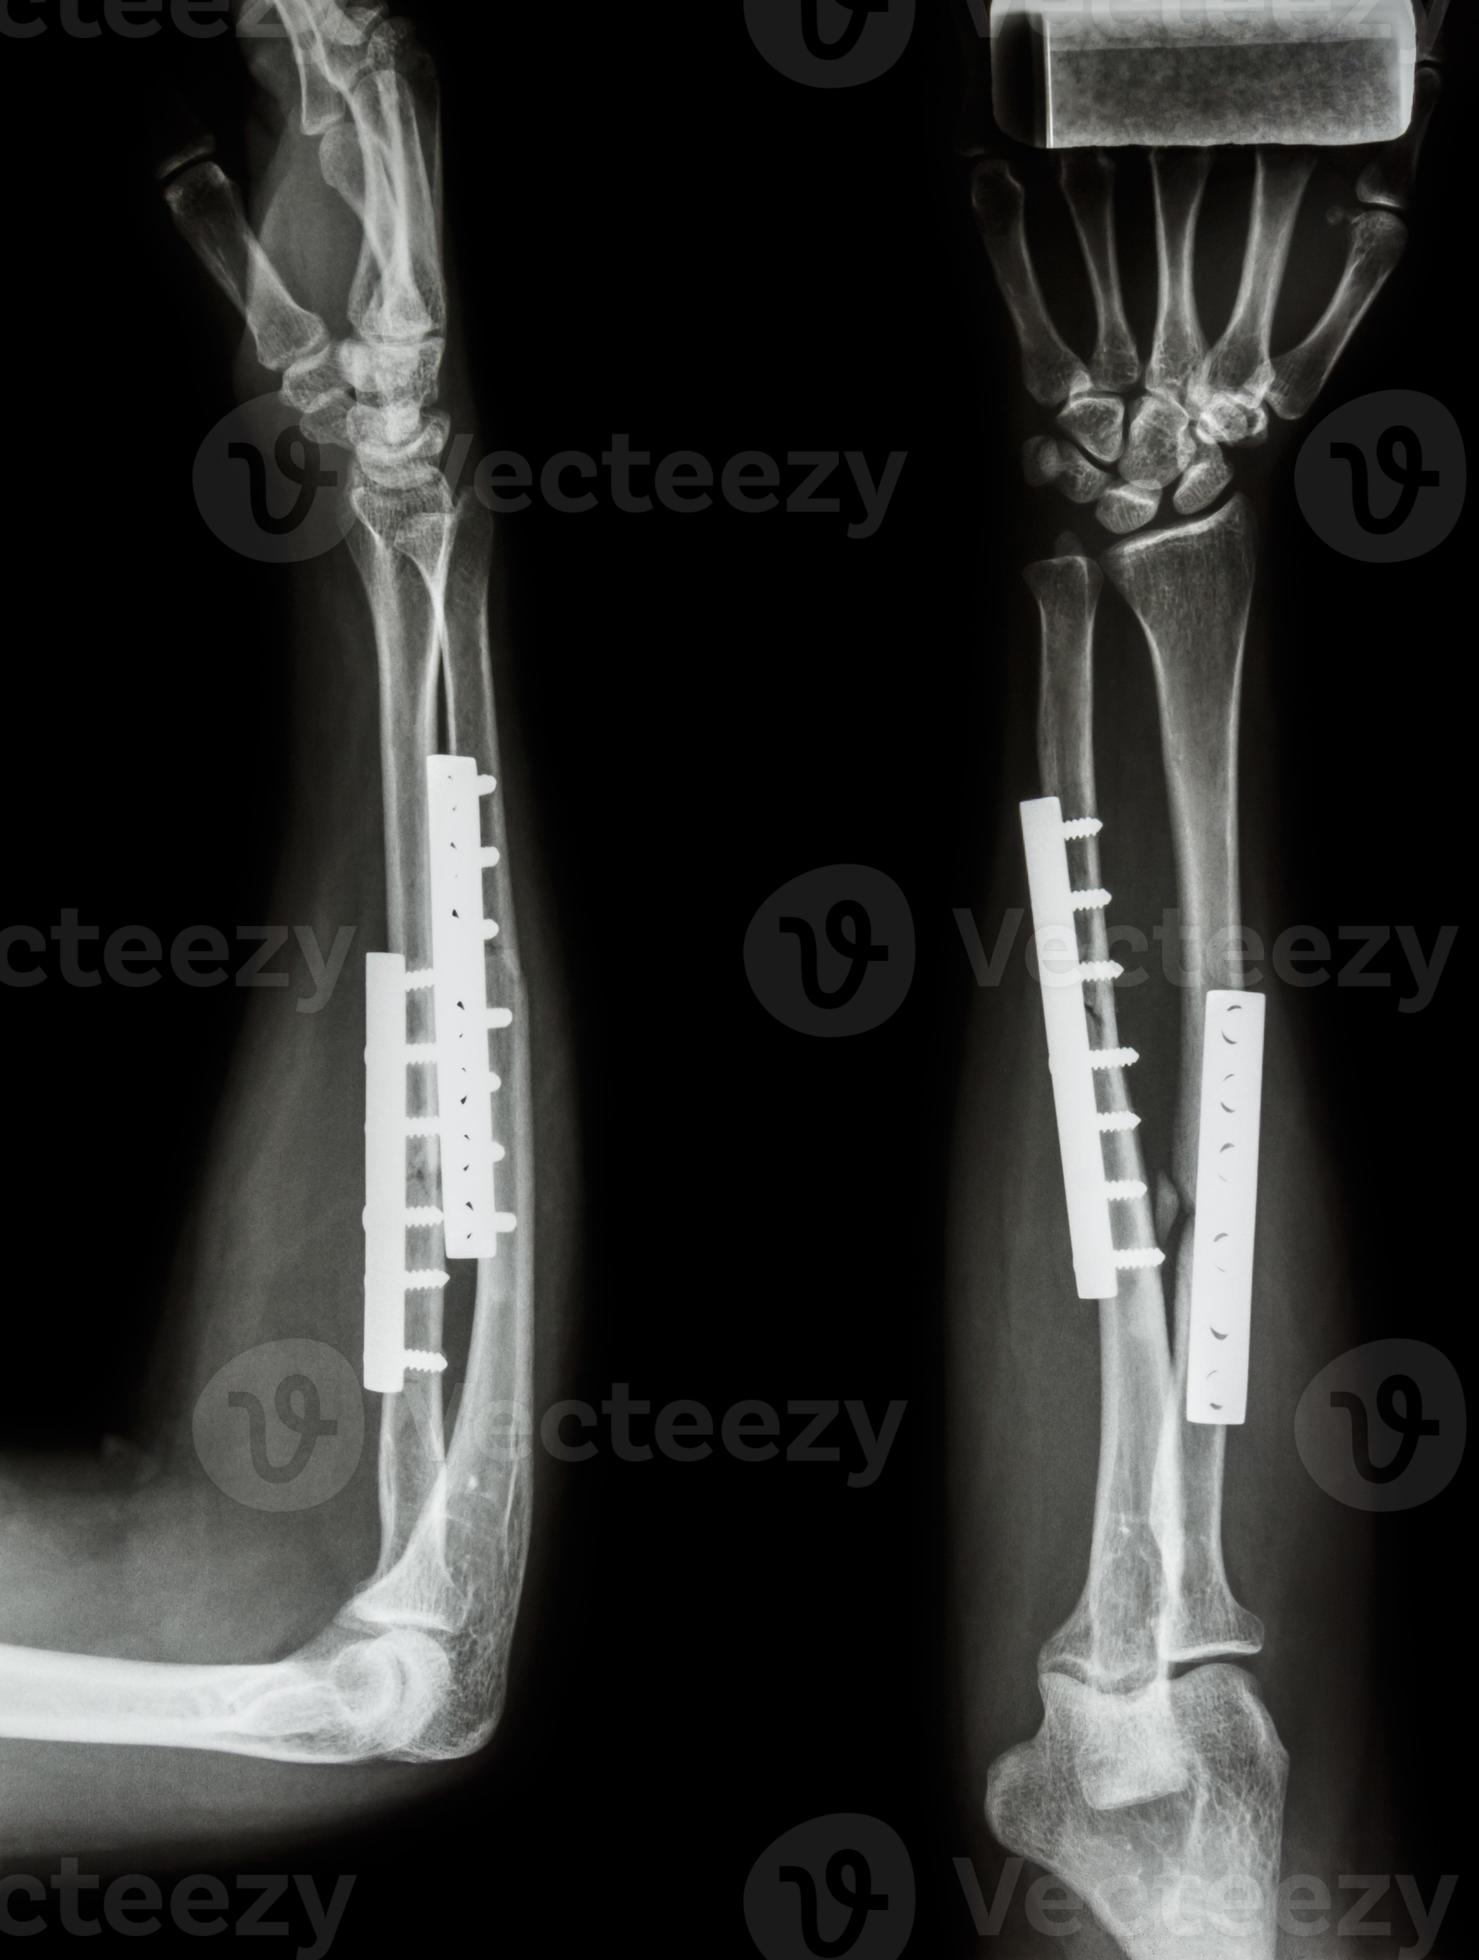

From www.vecteezy.com

Fracture shaft of radius and ulnar bone. It was operated and internal Radius And Ulna Fracture Operation  Volar approach to radius (henry) and subcutaneous approach to ulna; When both the radius and the ulna have a simple fracture pattern, either oblique or transverse (short oblique), possible techniques are: Distal radius fractures are the most common orthopaedic injury and generally result from fall on an outstretched hand. Diagnosis is made clinically and radiographically. Identify the etiology of radius. Radius And Ulna Fracture Operation.